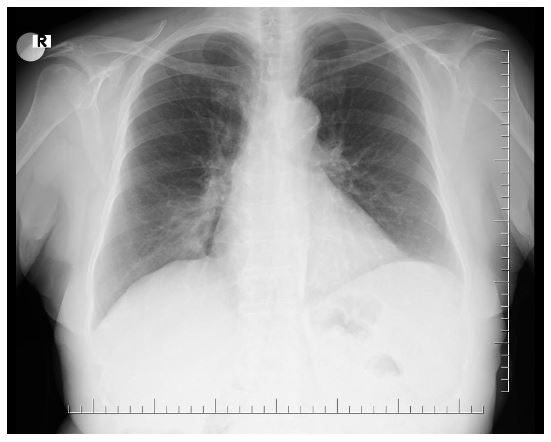

A 67-year-old woman presented with 2 years of productive cough and breathlessness. The patient was farmer, never smoked but had indoor cooking/heating smoke exposure history. She was treated with antibiotics and bronchodilators by her primary care physician but did not improve her symptoms. Lung auscultation and cardiac evaluation was unremarkable. Forced vital capacity (FVC),2.42 L (108%); forced expiratory volume in 1 sec (FEV1), 1.69 L (92%); FEV1/FVC ratio 70% in spirometry. Chest radiograph revealed paracardiac opacity in the right lower zone (Figure 1).